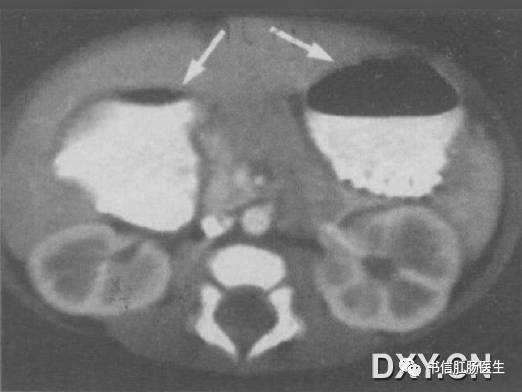

2.珠链征(串珠征)

★ 图示小肠梗阻患者,左侧卧位。气泡(箭头)为环状皱壁间的气体潴留。

■ 影像表现:珠链征可见于小肠梗阻患者的立位或侧卧位腹部 X 线平片,由一些斜行或水平走向的小气泡排列构成,形似一串珍珠,因此称为珠链征。

■ 征象解析:串状排列的气泡代表显著扩张的积液的小肠闭襻内嵌在黏膜皱壁之间的气体影,X 线摄影的半月效应使被液体围绕的气泡呈卵圆形或圆形。珠链征的形成取决于气体积液的小肠襻和小肠蠕动亢进同时并存。

■ 讨论:肠梗阻是一种常见的外科急腹症。X 线平片对梗阻的存在、性质、部位、程度及可能原因的诊断有一定帮助。无论什么性质的肠梗阻,基本 X 线表现为肠腔胀气、气液平面。若闭襻内充液多而气体少时,嵌在粘膜皱襞之间的气体影在 X 线立位或侧卧位腹部 X 线平片上可为一串圆形或卵圆形的透光区,称为珠链征。

认识珠链征的重要性与小肠梗阻的临床表现有关。小肠梗阻的典型临床表现有腹部柔软、膨隆和肠鸣音亢进。然而,主要为液体充盈的小肠完全性梗阻患者,由于没有气体产生气过水声,因而小肠扩张可能不明显,肠鸣音可能正常或减弱,但立位或侧卧位腹部 X 线平片仍有可能显示珠链征。了解珠链征这一重要 X 线表现,有助于避免遗漏临床诊断困难的病例。